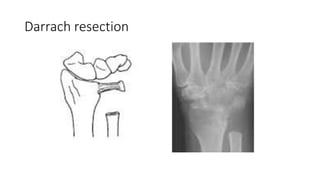

Darrach resection

• Procedure to stabilize unstable proximal ulnar segment after distal

ulnar excision

• Volar, distally based capsular flap attached to the ulna proximally

• Slip of the ECU tendon, based proximally or distally, passed through drill

holes in the ulna or wrapped around ulna

• PQ as a combination interposition-stabilizer

• Slip of FCU tendon, usually distally based and passed through drill holes in

ulna

• Combination of ECU tenodesis and dorsal transfer of PQ

• Procedure tostabilize unstable proximal ulnar segment after distal ulnar excision • Volar, distally based capsular flap attached to the ulna proximally • Slip of the ECU tendon, based proximally or distally, passed through drill holes in the ulna or wrapped around ulna • PQ as a combination interposition-stabilizer • Slip of FCU tendon, usually distally based and passed through drill holes in ulna • Combination of ECU tenodesis and dorsal transfer of PQ

• #42 SALVAGE elderly pt with limited activity- distal ulnar head excision (1.5-2cm ) Loss of grip strength, ulnar translation of carpus, ulnar impingement, ecu subluxation and pain, distal jn unstable